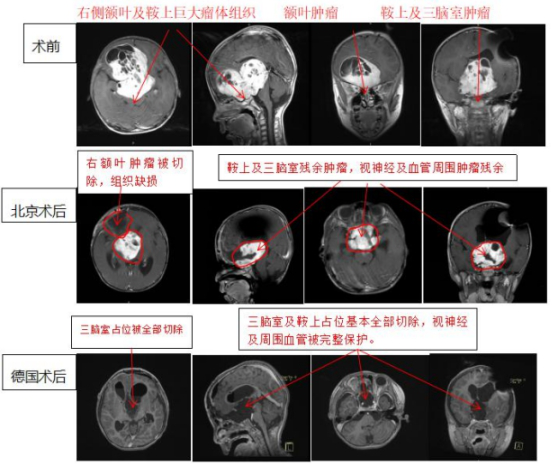

2018年,年僅5歲的兒童患視神經(jīng)膠質(zhì)瘤病情嚴(yán)重,國內(nèi)醫(yī)院均建議保守治療,為了更好的治療效果,后孩子父母聯(lián)系到INC,找到德國巴特朗菲教授。在巴特朗菲高超的手法下,手術(shù)順利,顯微手術(shù)切除率≥ 大概率!!! 并沒有有術(shù)中并發(fā)癥。

術(shù)前與術(shù)后MR影像對比顯示,切除率> 大概率。